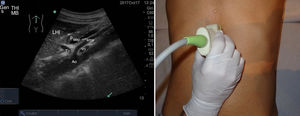

Para realizarla es necesario un ayuno previo de al menos 6-8 h para evitar en lo posible la presencia de gas intestinal y conseguir una máxima distensión de la vesícula. El paciente estará en decúbito supino, con abordaje subcostal pidiéndole que realice y mantenga inspiración profunda para obtener imágenes óptimas (fig. 5); en ocasiones, es necesario el abordaje intercostal o el decúbito lateral izquierdo19.

La vía biliar (colédoco) se localiza en un corte oblicuo, paralela y por delante de la porta, junto a la arteria hepática (presentan grosores similares y el Doppler puede ayudar a diferenciarlas). Si se gira el transductor 90° se visualizarán estas estructuras transversalmente (imagen del «ratón Mickey») (fig. 6). El calibre del colédoco debe ser < 6mm, excepto en pacientes colecistectomizados (< 10mm). Los conductos biliares intrahepáticos no se ven en condiciones normales. La vesícula biliar tiene forma ovalada (aunque variable20), sin ecos en su interior, < 4-5cm de diámetro transversal (el más fiable) y < 10cm de diámetro longitudinal. La posición del fondo es variable, por lo que se deben hacer diferentes cortes oblicuos hasta conseguir un corte longitudinal de la vesícula.